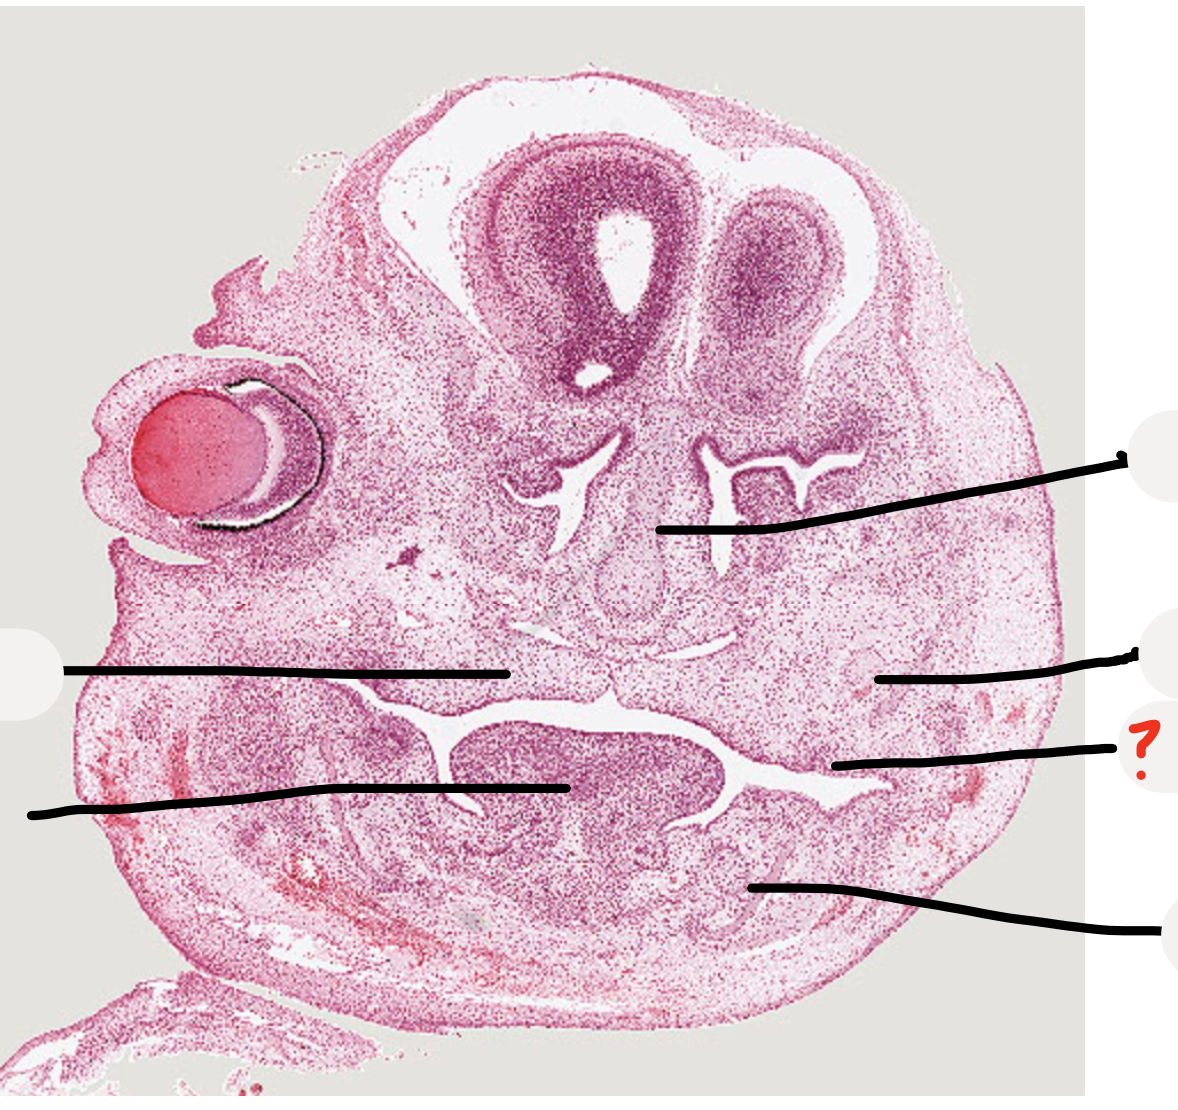

35

developing mandible

36

inferior alveolar nerve

37

this will be the sulcus

38

look at this inferior alveolar nerve next to the developing mandible

39

what are these?

Remnants of nasal capsule

40

Condensed ectomesenchymal cells that will make dentine and pulp

41

Epithelial cells that will form ameloblasts and make enamel